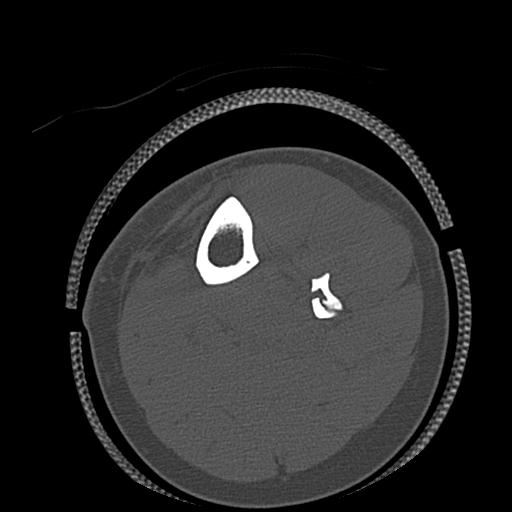

49554 3/13 膝 4R 3/16 4R 1/18 2R 78歳男性 膝蓋骨骨折